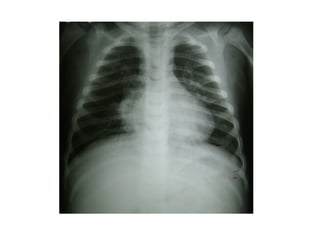

Radiografia

 Não precisa ser feita na criança tratada em casa.

 Radiografias em perfil não precisam ser feitas rotineiramente,

em todos os casos.

 A imagem radiológica não distingue etiologia viral ou

bacteriana.

 Não se recomenda radiografias de controle, exceto para

pneumonias complicadas, como com derrame pleural ou

atelectasia.

Manifestações radiográficas